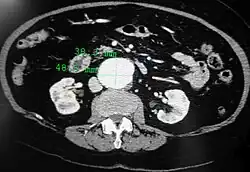

A transverse contrast enhanced CT scan demonstrating an abdominal aortic aneurysm of 4.8 by 3.8 cm